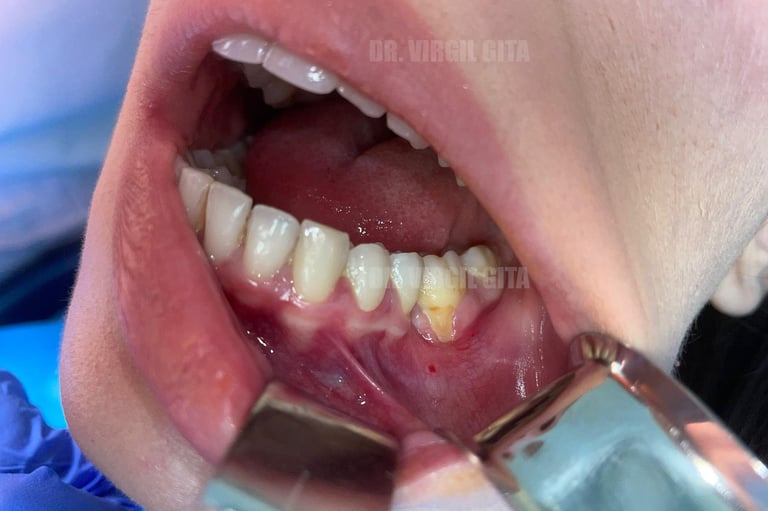

Tratament retractie gingivala post tratament ortodontic cu lambou tractionat coronar si grefa de tesut conjunctiv prelevata de la nivelul palatului + membrana PRF